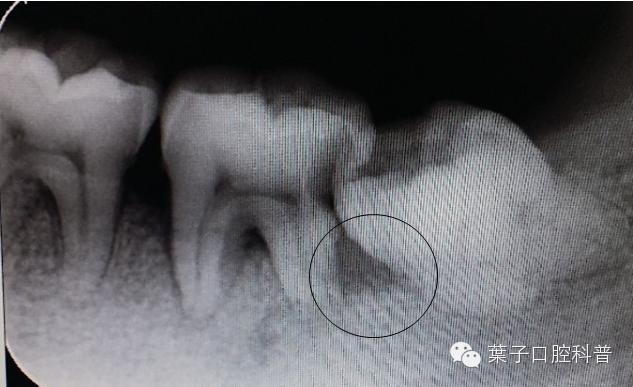

第二磨牙与智齿之间牙槽骨吸收

拔智齿十大危害,拔智齿利与弊